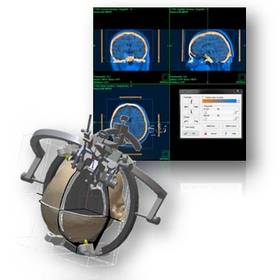

inomed Planungssoftware iPS

Moderne bildgebende Verfahren in Kombination mit den Entwicklungen im Bereich der elektronischen Datenverarbeitung verhalfen der stereotaktischen und funktionellen Neurochirurgie zum Durchbruch. Denn erst sie ermöglichten präzise und gewebeschonende Eingriffe wie zum Beispiel die Tiefe Hirnstimulation (THS) am menschlichen Gehirn.

Die visuelle Planung einer Operation am Gehirn ist in der Stereotaxie >> unerlässlich für einen sicheren und zielführenden Eingriff, dies gilt im Besonderen für die THS. Die Vorbereitung eines Eingriffs – ob THS oder stereotaktische Biopsie – mittels des inomed Planungssystems iPS ist dabei der erste Schritt für Neurochirurgen, um patientenschonende und lebenserhaltende Therapiemöglichkeiten zu realisieren.

Die hohe Qualität der Bilddarstellung zeichnet das inomed Planning System (iPS) aus. Die automatische Zusammenführung verschiedener Bildmodalitäten ermöglicht eine schnelle und sichere Verifikation der geplanten Zugänge. Diese Zugänge sind für eine erfolgreiche THS zwingend notwendig. Auf Wunsch lassen sich anatomische Atlanten über patientenbezogene Daten projizieren. Dies erlaubt wiederum die Verifikation anhand anatomischer Grundlagen.

Die Planungssoftware iPS von inomed unterstützt sämtliche Planungsansätze, ob „freehand“, funktionell, atlasbasiert oder metabolisch orientiert. Hierfür stehen jeweils verschiedene Möglichkeiten zur Verfügung, die einander ergänzen können. Auch die Option einer Vorabplanung mit Übertragung auf die stereotaktische Bildmodalität gewährleistet die rasche aber genaue Zielpunktplanung am Tag des Eingriffs (THS, Biopsie etc.).

Die Möglichkeit einer schnellen Generierung von 3D Ansichten des Patientenschädels hilft bei der Verifikation der Zielpunktplanung im Zuge der THS. Durch Projektion des verwendeten Stereotaxie-Systems bekommt der Anwender eine realistische Darstellung über Anordnung und Auswirkung der Trajektorie-Planung auf den Systemaufbau.